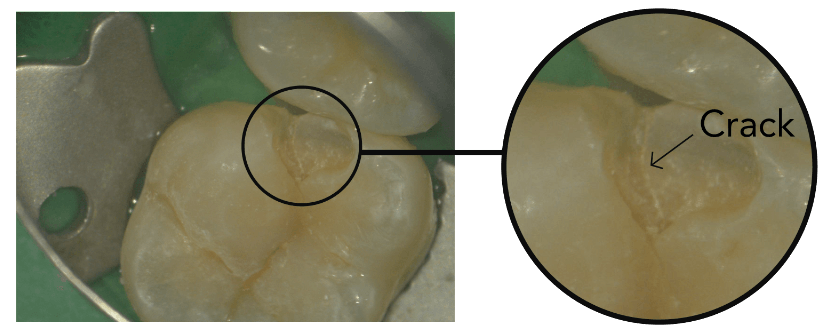

Problemer som vanligvis er usynlige til de blir akutte:

Riss og sprekker i tannemaljen

Nøyaktig diagnose Vi ser problemet før det blir akutt

Tidlig oppdagelse Enklere og billigere behandling

Opptil 20× forstørrelse. Avdekker det som er usynlig for det blotte øye.

"Det øyet ikke ser —

kan mikroskopet avsløre"